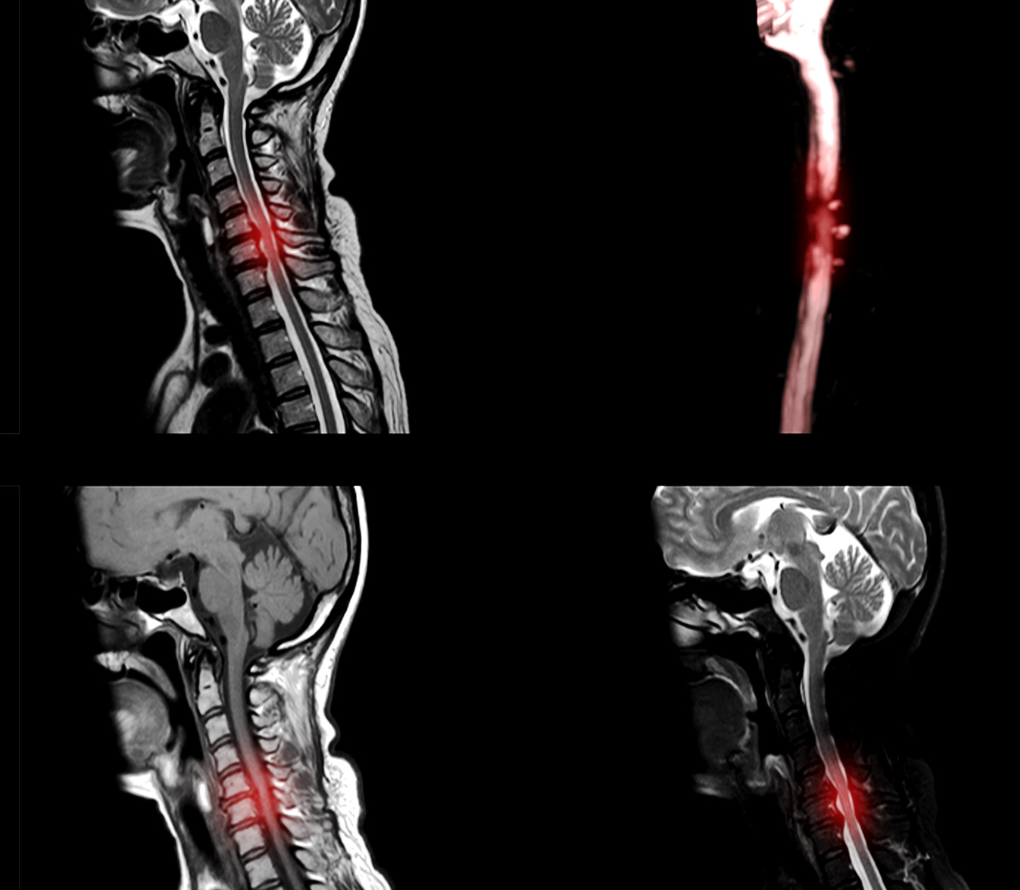

Cervical myelopathy is a condition where the spinal cord in the neck (cervical spine) becomes compressed or squeezed. The spinal cord is like the body’s “information highway,” carrying signals between the brain and the rest of the body. When it gets compressed, it can cause problems with walking, hand function, balance, and sometimes bladder or bowel control.

It is most often due to age-related changes in the spine (also called cervical spondylotic myelopathy). Unlike simple neck pain or pinched nerves, myelopathy affects the spinal cord itself, making it more serious. However, with timely diagnosis and treatment, patients can maintain good quality of life.